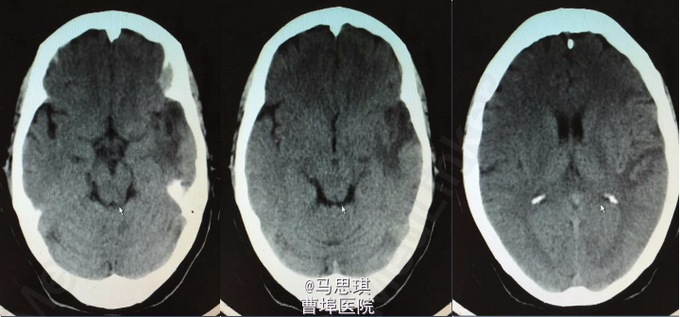

复查CT(3周后):左侧额颞顶叶片状脑梗塞密度较前片略降低。 3周后,患者行左侧脑膜中动脉血管畸形栓塞术,但因患者于部分供血血管造影时述左耳疼痛明显,放弃有明显临床症状供血血管栓塞术,随后出院。嘱氯吡格雷75mg Qd 立普妥 20mg qd 讨论:对于此类特殊病因的卒中患者如何评估溶栓风险?如何评估双抗风险?